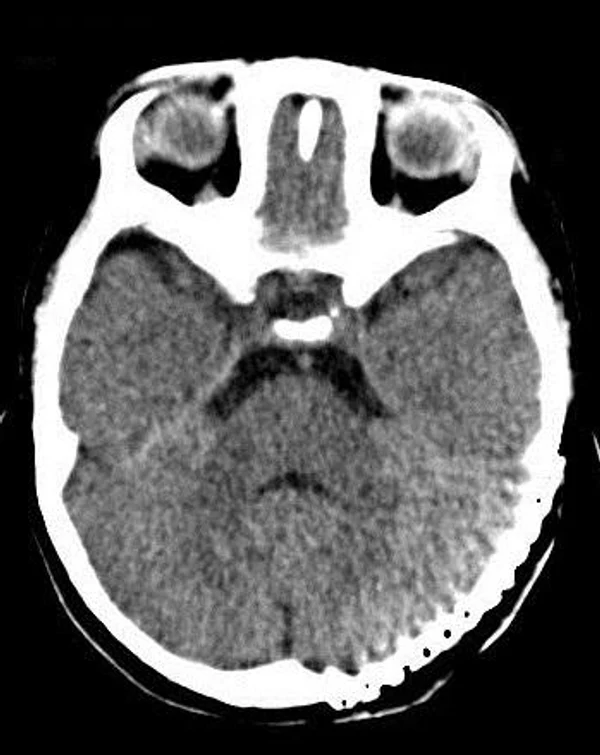

Удаление опухолей черепаВ качестве примера лечения пациентов с опухолями черепа привожу личное наблюдение пациента грудного возраста с опухолью черепа. В возрасте 1 мес. у ребёнка в затылочной области слева родителями обнаружено плотное образование диаметром 5 мм. За 3 мес. до госпитализации образование значительно увеличилось в размерах. При поступлении в возрасте 6 мес. в затылочной области слева (в проекции лямбдовидного шва) имеется безболезненное, плотное, неподвижное, бугристое образование размерами 5 х 4 х 2 см. При КТ и МРТ головы выявлена опухоль черепа в области астериона слева, обладающая преимущественно интракраниальным ростом (рис. 30 а). Ребёнку выполнено удаление опухоли черепа (рис. 30 б). Образовавшийся дефект черепа больших размеров закрыт перфорированной титановой пластиной (рис. 30 в). При наблюдении пациента в течении 2-х лет рецидива заболевания и деформации черепа не отмечалось.